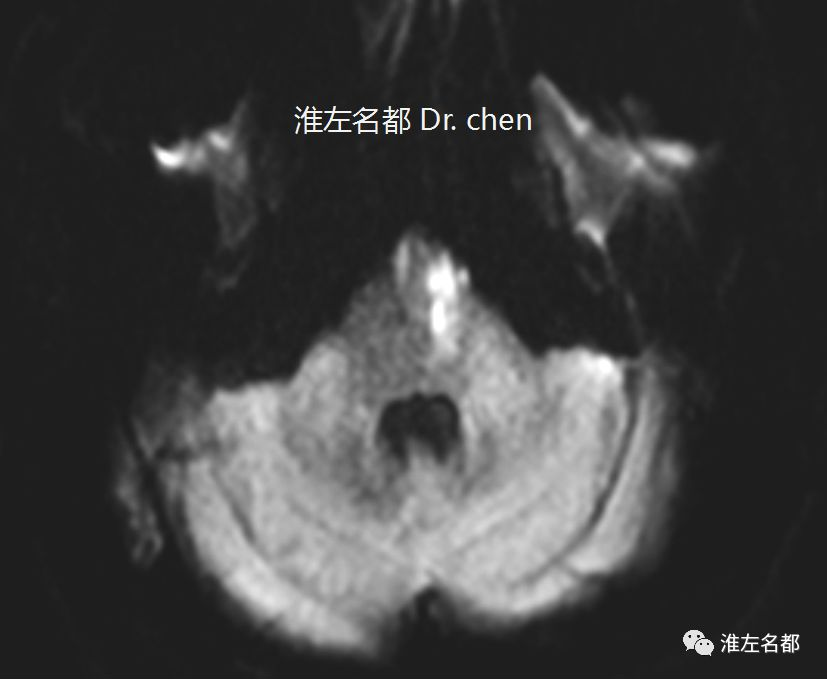

△DWI:左侧脑桥梗死

DWIleft pontine infarction